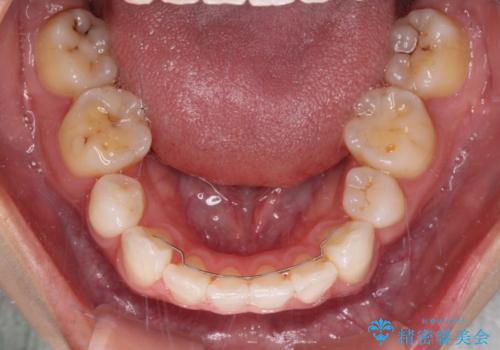

当初はインビザラインによる矯正治療をご希望でしたが、正中を合わせたいことや、口元の突出感を改善したいことから、ワイヤー矯正を強く推奨しました。

治療期間は2年に満たず、スッキリとした口元に仕上がりました。